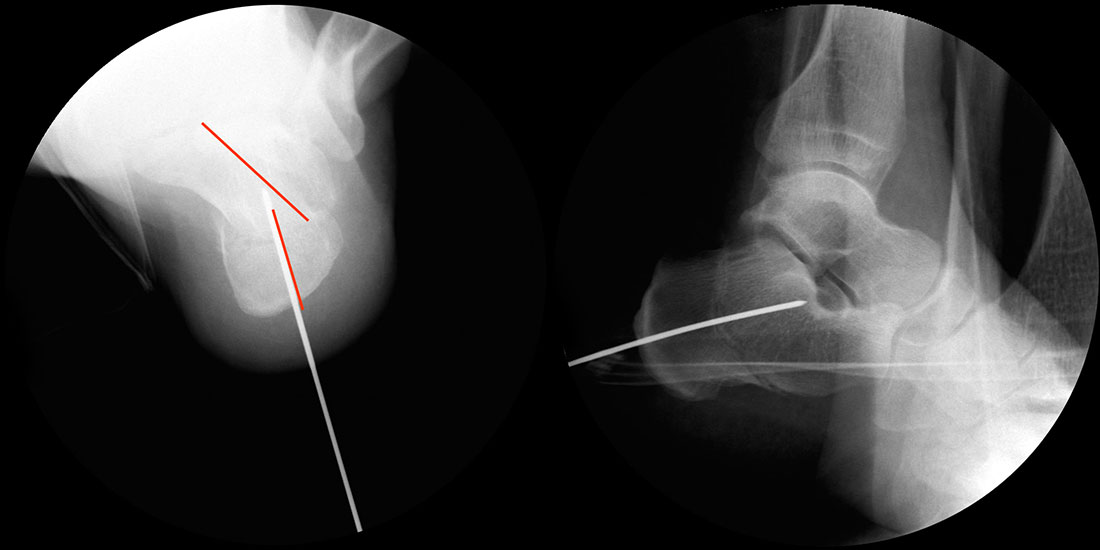

Röntgenaufnahmen des Fußes d.p., streng seitlich und schräg unter Belastung. Saltzmann Aufnahme zur Beurteilung der Rückfussachse.

Operationsplanung anhand der Röntgenaufnahmen unter Beachtung wichtiger radiologischer Landmarks wie Rückfussachse, Metatarsale I – Talushals-Achse im dp und lateralen Strahlengang (Abbildung 1 und 2).

Abbildung 1

Abbildung 2